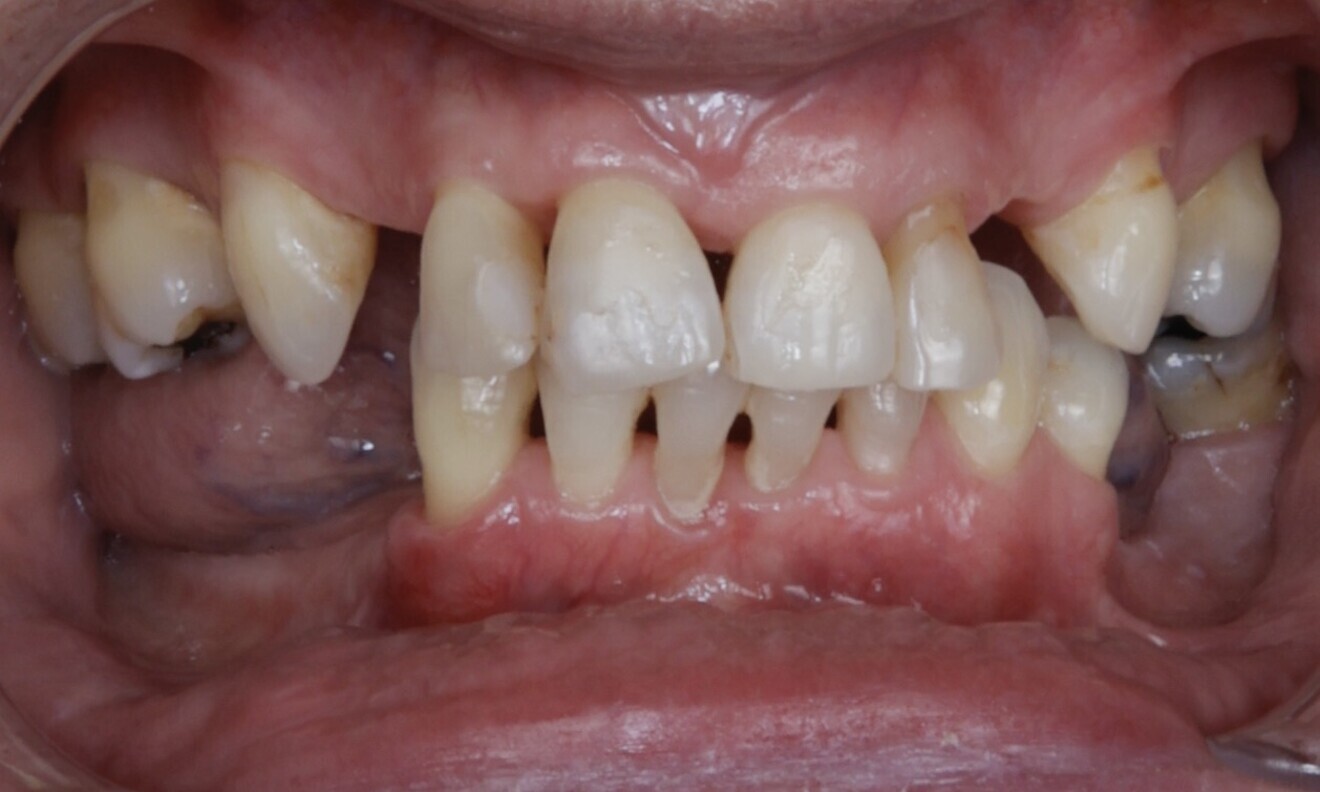

Figs. 1–3: The initial situation showed significant spacing between the teeth

Fig. 2

Fig. 3

Initial situation

A healthy 61-year-old female patient with no significant medical history and who took no medications and had no known systemic diseases or risk factors such as smoking that could compromise treatment outcomes came to our clinic. She was concerned about the mobility of her teeth and their appearance. She also reported finding it difficult to eat properly, affecting her daily life. The patient’s primary focus was improving the aesthetics of her teeth to achieve a natural appearance that would complement her facial features. She also prioritised restoration of proper function to eat comfortably without difficulty. She was opposed to wearing a denture and desired a long-term solution that would maintain her quality of life while ensuring stable teeth and optimal oral health.

In the extra-oral examination, a medium smile line was observed with prominent spaces between the teeth owing to tooth loss and the presence of black triangles (Figs. 1–3). Intra-orally, the patient presented with generalised plaque accumulation and inflammation, affecting approximately 30% of the oral cavity. Periodontal examination revealed areas of localised bleeding on probing, indicating active inflammation. Tooth mobility was evident for multiple teeth, consistent with the patient’s history of periodontal disease.

The patient wore a removable restoration in the maxillary arch and presented with anterior retainers in both the maxillary and mandibular arches owing to tooth mobility caused by periodontal disease. Teeth #15, 13, 23, 25, 27, 36, 35, 44, 45, 46 and 47 were missing. Additionally, the patient presented with several dental fillings (Figs. 4–7).